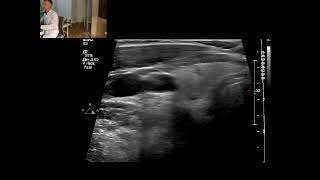

–í–ł–ī–Ķ–ĺ–∑–į–Ņ–ł—Ā—Ć –£–ó–ė –°–ī.Ű.4 4/tbŰ.JŰ`Ű Ű t. ňJ’�TźQ� Õ video

–í–ł–ī–Ķ–ĺ–∑–į–Ņ–ł—Ā—Ć –£–ó–ė - –°–ĺ–Ľ–ł–ī–Ĺ—č–Ļ —É–∑–Ķ–Ľ - TIRADS 4

–í–ł–ī–Ķ–ĺ–∑–į–Ņ–ł—Ā—Ć –£–ó–ė - –°–ĺ–Ľ–ł–ī–Ĺ—č–Ļ —É–∑–Ķ–Ľ - TIRADS 4 –í–ł–ī–Ķ–ĺ–∑–į–Ņ–ł—Ā—Ć –£–ó–ė - –°–ĺ–Ľ–ł–ī–Ĺ—č–Ļ —É–∑–Ķ–Ľ - TIRADS 4

–í–ł–ī–Ķ–ĺ–∑–į–Ņ–ł—Ā—Ć –£–ó–ė - –°–ĺ–Ľ–ł–ī–Ĺ—č–Ļ —É–∑–Ķ–Ľ - TIRADS 4

–í–ł–ī–Ķ–ĺ–∑–į–Ņ–ł—Ā—Ć –£–ó–ė - –°–ĺ–Ľ–ł–ī–Ĺ—č–Ļ —É–∑–Ķ–Ľ - TIRADS 4 –í–ł–ī–Ķ–ĺ–∑–į–Ņ–ł—Ā—Ć –£–ó–ė - –°–ĺ–Ľ–ł–ī–Ĺ—č–Ļ —É–∑–Ķ–Ľ - TIRADS 4